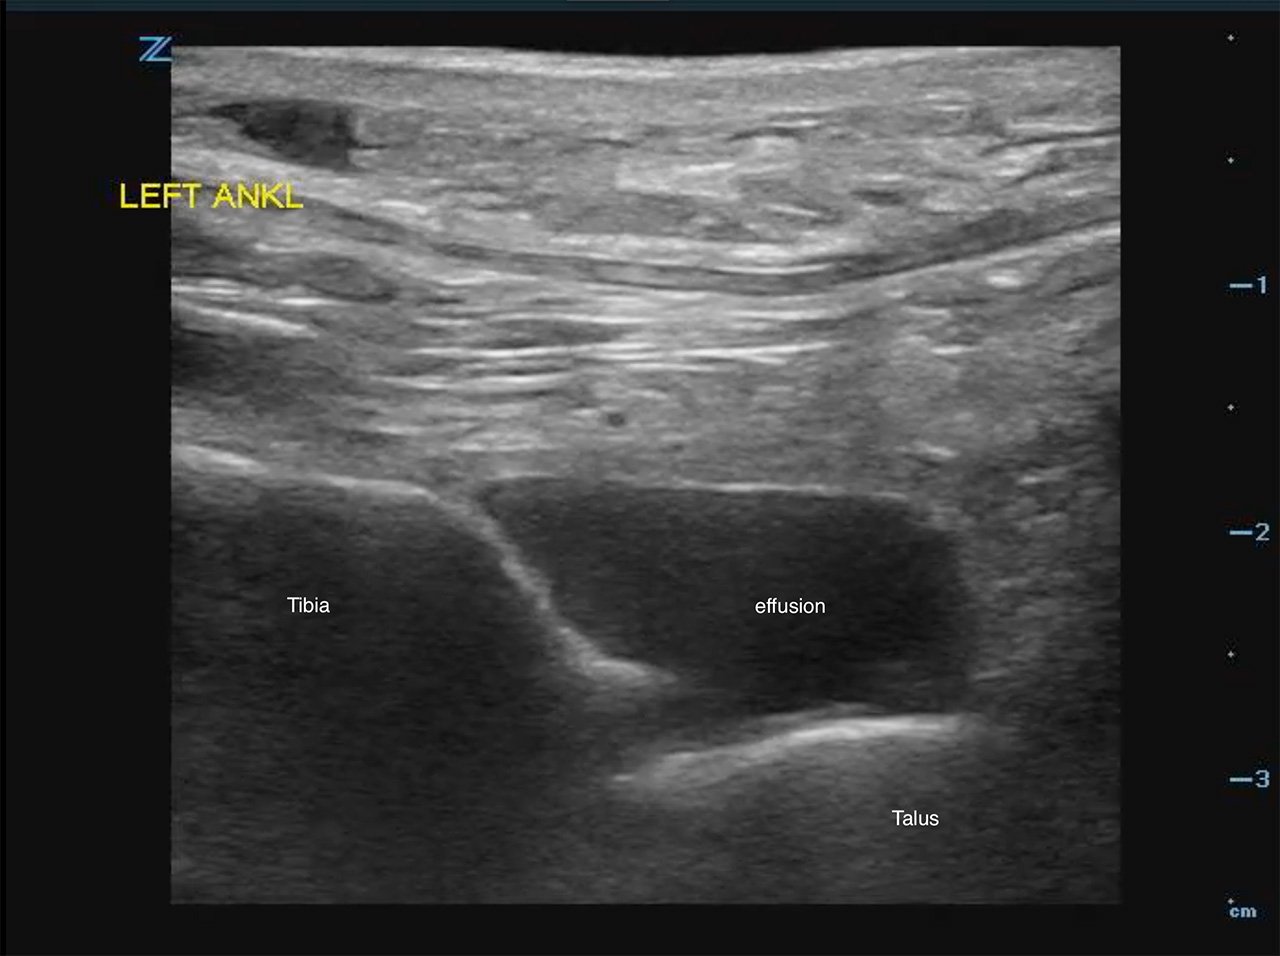

- Identify the hyperechoic tibial cortex and scan distally to the joint space and identify the next shadowing hypoechoic structure, the talus. Fluid should appear anechoic in the tibio- talar space. (Fig. 2a,b)

- Figure 2b. Ultrasound demonstrating tibiotalar effusion